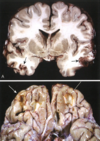

Figura 28.2 Hidrocefalia. Ventrículos laterales dilatados observados en corte frontal a través de la región centraI del tálamo.

Si la hidrocefalia se produce en un niño antes del cierre de las suturas craneales, la cabeza aumenta de tamaño. Por el contrario, después del cierre de las suturas, la hidrocefalia produce expansión de los ventrículos y aumento de la …… intracraneal, sin cambios en el perímetro cefálico